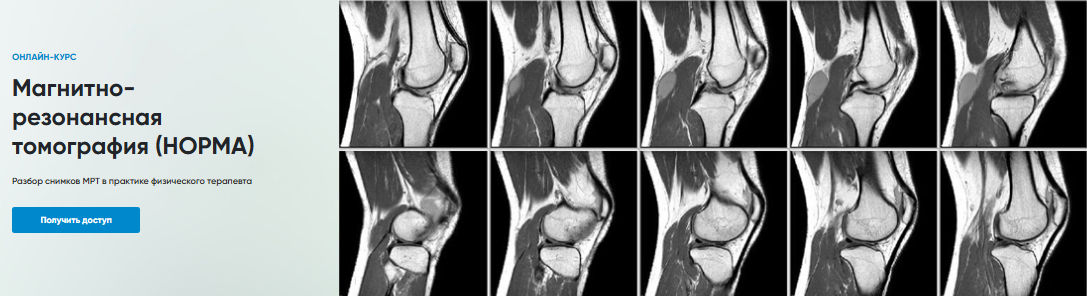

Магнитно-резонансная томография (НОРМА)

Разбор снимков МРТ в практике физического терапевта

Программа

1. МРТ Коленного сустава

2. МРТ Голеностопного сустава

3. МРТ Запястье

4. МРТ Локтевого сустава

5. МРТ Плечевого сустава

6. МРТ Поясничного отдела позвоночника

7. МРТ Тазобедренного сустава

8. МРТ Шейного отдела позвоночника